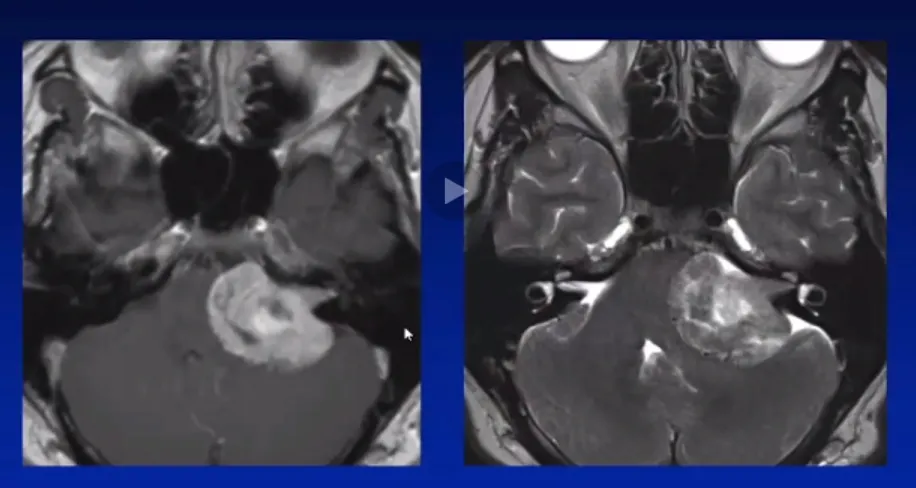

36岁患者卢卡遭遇持续耳鸣与进行性听力下降,经检查发现罹患直径超过3cm的巨大听神经瘤。该病例中,肿瘤已长期潜伏发展。

当听神经瘤生长至3cm以上时,通常已对脑干、小脑等生命中枢产生严重压迫。肿瘤与面神经、听神经及其他颅神经之间形成复杂的生物学粘连,而非简单的推挤关系。

在部分病例中,为最大限度保护神经功能,医生可能选择次全切除方案,残留部分辅以伽玛刀放疗。但需要警惕的是:若伽马刀治疗后肿瘤复发,二次手术将面临更大挑战——放射线导致的瘢痕组织会使肿瘤与脑干、神经粘连更加紧密,分离难度显著增加,手术风险急剧上升。